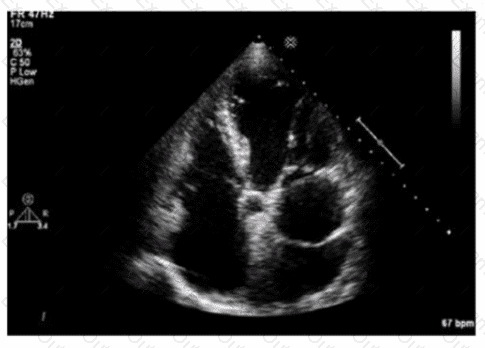

Based on this video, what is the estimated right atrial pressure in millimeters of mercury (mmHg)?